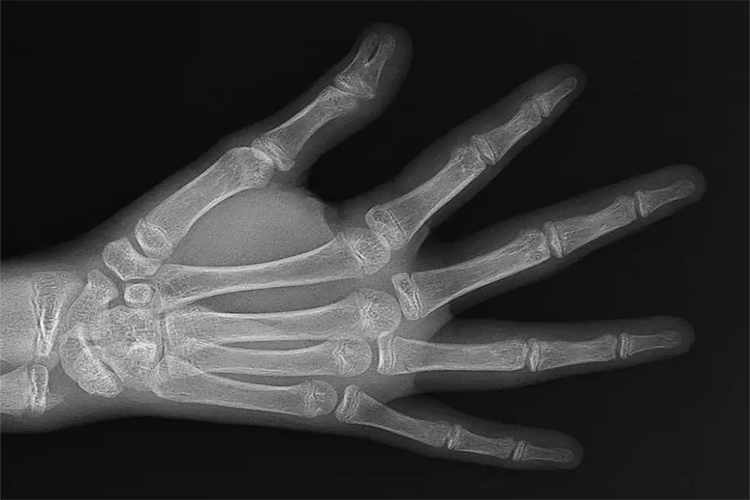

骨骺线为干骺端与骨骺间的软骨投影,儿童期呈透明带,称为骨骺板,随年龄的增大逐渐变窄呈透亮线,称为骨骺线,最终消失。骨骺位于长骨两端或突出部,初始多为软骨,随年龄增长,二次骨化中心逐渐增大形成骨松质,边缘也逐渐变光整,最后与骨干愈合。

骨骺线闭合情况对评估骨骼发育情况有重要意义,随年龄的增加,长骨干骺端的软骨次级骨化中心按一定顺序及骨解剖部位有规律地出现。长骨的生长主要由长骨干骺端的软骨骨化,骨膜下成骨,使长骨增长、增粗,当骨骺与骨干融合时,骨骺线闭合,标志长骨停止生长。骨化中心的出现可反映长骨的生长成熟程度,用X线检查测定不同年龄儿童长骨干骺端骨化中心的出现时间、数目、形态的变化,并将其标准化,即为骨龄。